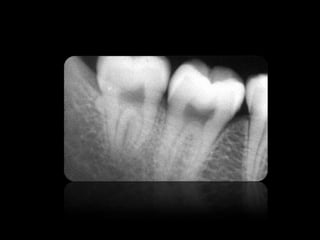

CARIES

ABSCESO PERIAPICAL